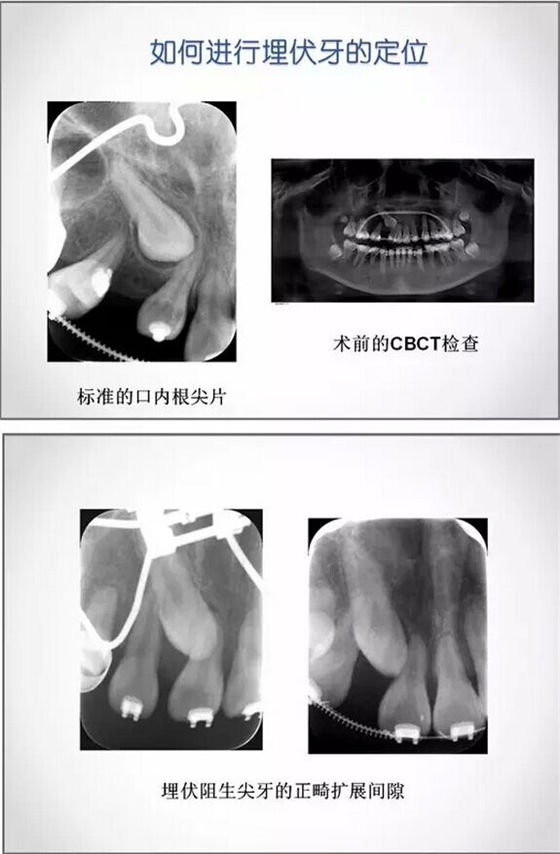

埋伏牙正畸治療中的外科開窗術

1.png

2.png

3.jpg

4.jpg

5.png